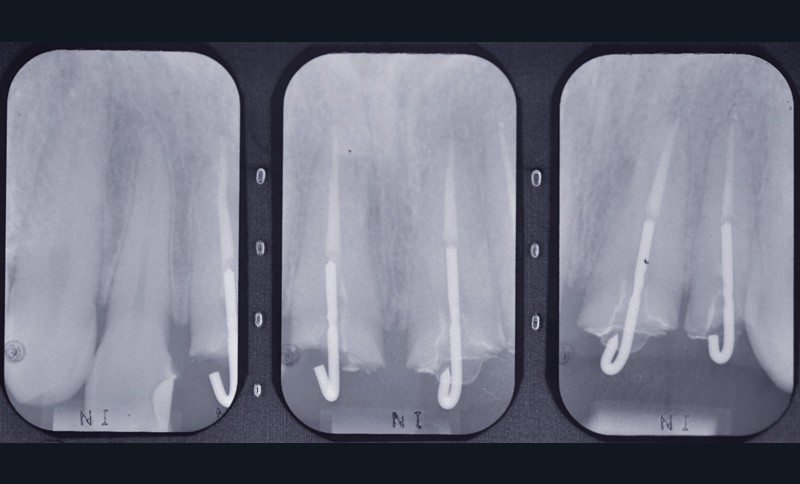

Dans un premier temps, sur la base d’un examen clinique et radiologique (fig. 2b), de modèles d’étude (si nécessaire montés sur simulateur), la conservation de piliers dentaires futurs, pulpés ou dépulpés, partiels ou périphériques, est évaluée, avec l’assistance possible de thérapeutiques orthodontiques et parodontales, avant le recours à des piliers implantaires.